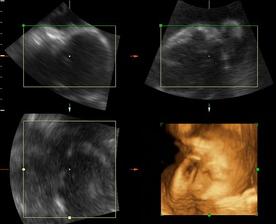

a dnes, 16.10.2008, teda v 38. týždni, padlo definitívne rozhodnutie o mene...skôr moje rozhodnutie ako tatkove...🙂...takže naša prvorodená dcérka sa bude volať Ema Silvia...🙂

a z Emy Silvie je nkoniec Natalka...teraz uz 4 a pol roka, netrpezlivo cakajuca na braceka, ktory restie v brusku...🙂